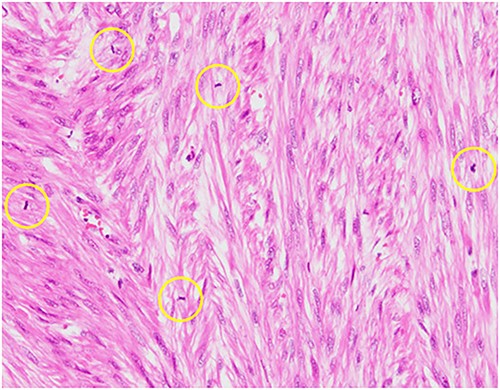

Pathological reports revealed a smooth muscle tumor with 31 mitotic figures per 10 high-power fields, but lacking cytologic atypia and tumor cell necrosis (Fig. 3). Based on the histological staining results, the patient was diagnosed with a retroperitoneal mitotically active leiomyoma.

Hematoxylin–eosin staining, ×10 showing increased mitotic activity (yellow circles).

Retroperitoneal mitotically active leiomyomas can be observed in postmenopausal women. Leiomyomas are non-cancerous monoclonal tumors that arise from smooth muscle cells and fibroblasts that can exhibit various types of smooth muscle differentiation. Although various atypical localizations of leiomyomas have been reported, growth in the retroperitoneum is extremely rare [4]. Additionally, the etiopathogenesis of primary retroperitoneal leiomyomas has not been fully elucidated. In general, classic leiomyomas have the following features: a mitotic index of <5 mitotic figures per 10 high-power fields, mild cytologic atypia and no tumor cell necrosis. In our patient, the leiomyoma had 31 mitotic figures per 10 high-power fields, but lacked cytologic atypia and no tumor cell necrosis, which warranted the classification of mitotically active leiomyoma [5, 6]. Progesterone is thought to influence the mitotic index of smooth muscle tumors [7]; consequently, leiomyomas are more likely to have an increased mitotic count if they are excised during the secretory phase of the menstrual cycle or pregnancy, or when patients receive exogenous progestins [5, 8, 9]. The previous findings explain why mitotically active leiomyomas are rarely observed in postmenopausal women [3]. To the best of our knowledge, this is the first reported case of a retroperitoneal mitotically active leiomyoma in a postmenopausal woman.